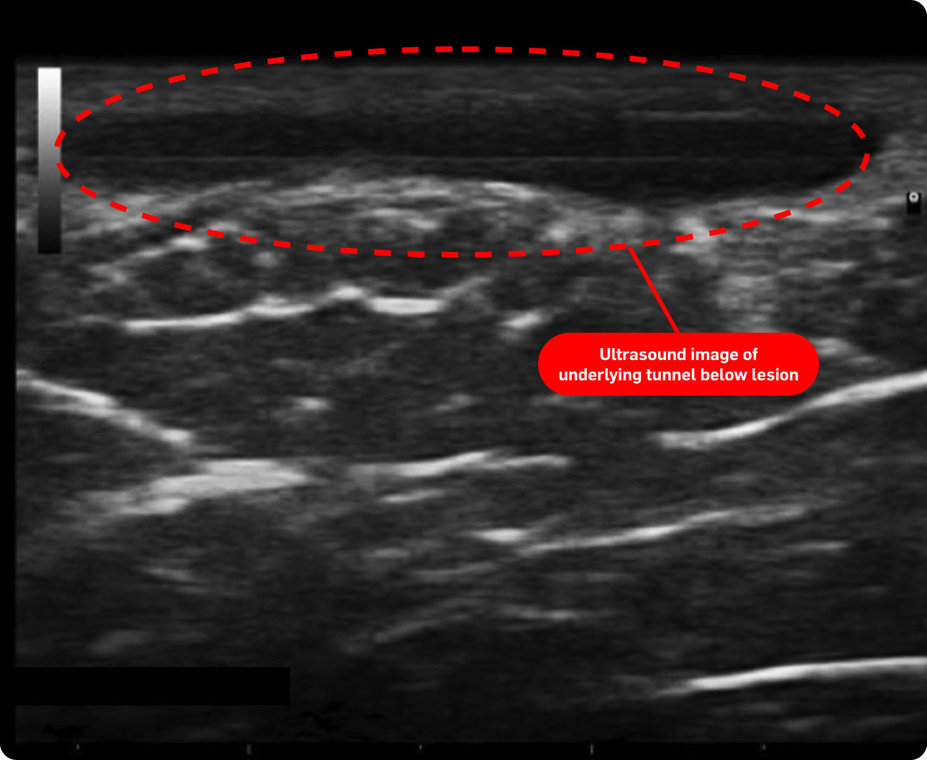

In one study, nearly 45% of patients were reclassified to be moderate or severe* after an ultrasound exam (n=38)1†

*As measured by patients going from Hurley Stage I to II or III.1

†Based on Spanish diagnostic study of adult patients diagnosed with HS (N=143). The number of patients who may have been reclassified to a lower Hurley stage was not reported/noted by the study. The mean number of fistulas on ultrasound compared to clinical exam was not statistically significant.1

‡Images are from a 2015 Martorell study, not the same study as the data presented above.2